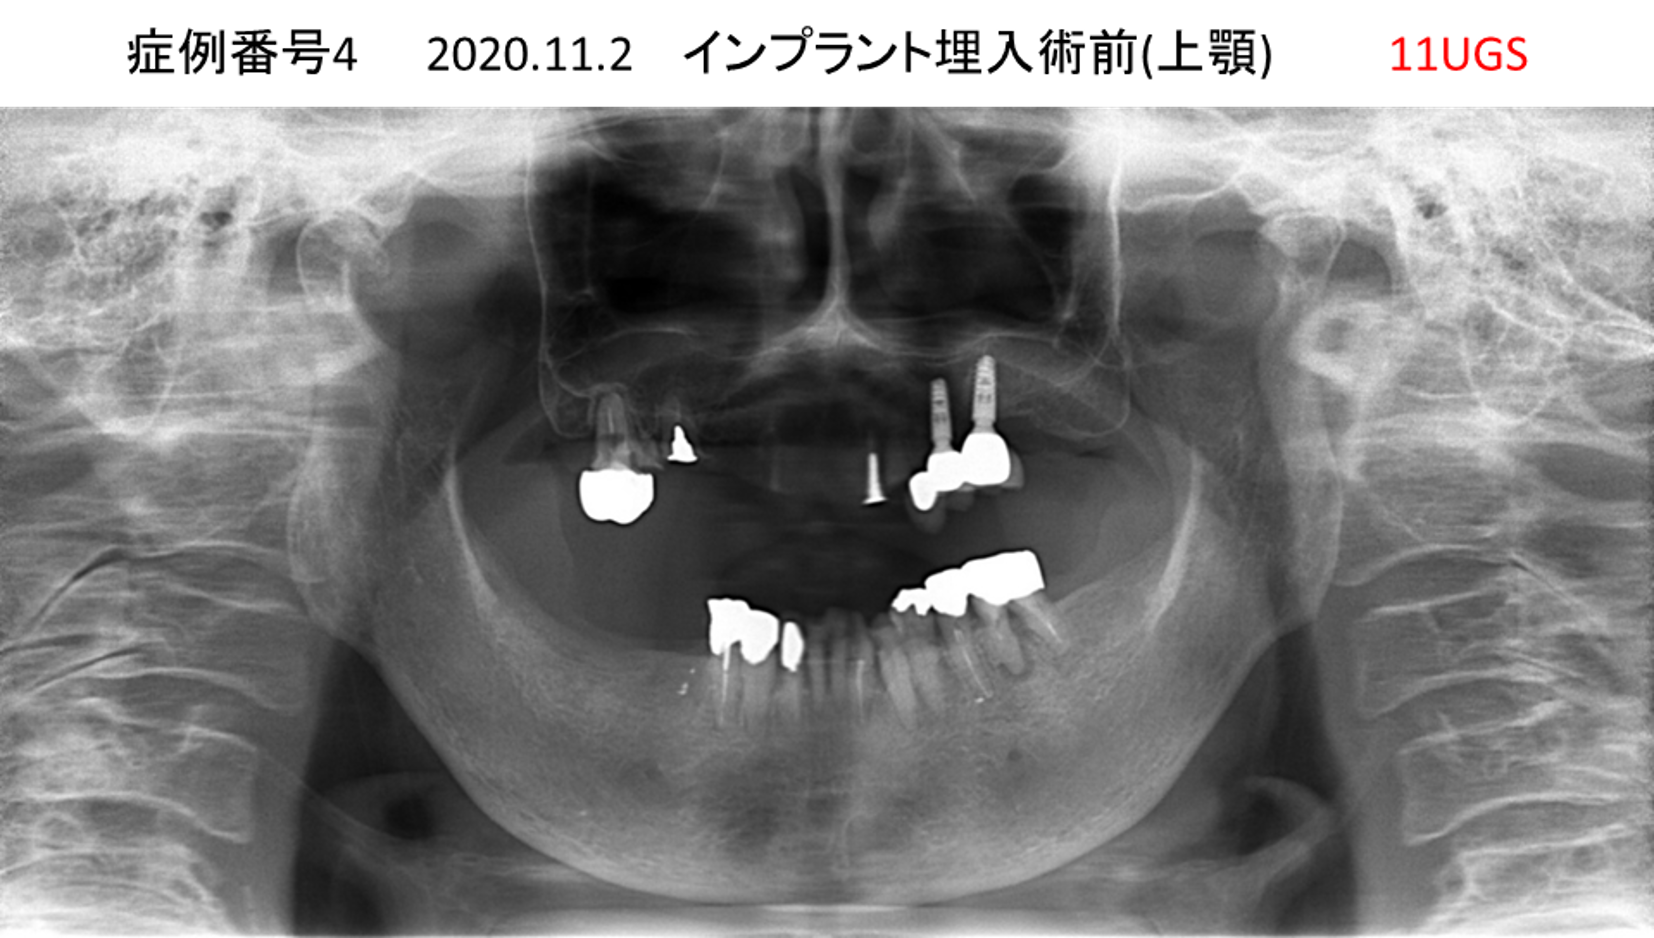

上の前歯が揺れてきてかめない患者様のインプラント症例

| 治療名称 |

インプラント |

| 治療費用 |

440万円+税 |

| 治療期間 |

6か月 |

| 患者さんの症状(主訴) |

上の前歯が揺れてきた。かめない |

| 治療内容 |

サイナスリフト、GBR、インプラント、即時荷重 |

| 治療結果 |

上の前歯の揺れが収まった。奥歯でしっかり噛める。 |

| 治療の注意点(リスク/副作用) |

インプラントが壊れたら再治療が必要 |